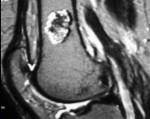

Диагностика энхондром, как правило, несложна. На рентгенограммах длинных трубчатых костей выявляется центрально расположенное облаковидное просветление. В зоне просветления могут обнаруживаться более темные участки - очаги кальцификации. Опухоли в области коротких трубчатых костей обычно выглядят однородными и занимают большую часть поперечника или весь поперечник кости. Кортикальный слой не нарушен. На КТ кости определяется аналогичная картина, преимуществом компьютерной томографии является возможность более подробно рассмотреть структуру энхондромы.